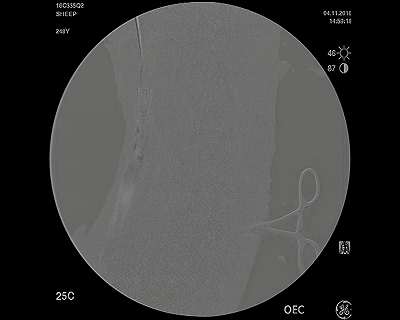

向上的靜脈造影圖,顯示VenoValve的通暢性,允許正常定向的血流返回心臟